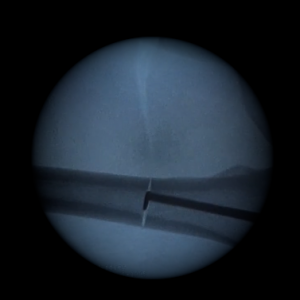

Intramedullary saw kit

Our intramedullary saw kit makes it easier to perform osteotomies thanks to the gradual emergence of the teeth.